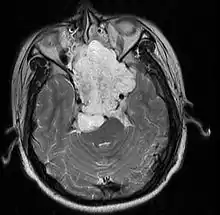

| MRI of extensive clival chordoma in 17-year-old male patient, axial view. Tumor in the nasopharynx extending from nasal cavity to brainstem posteriorly is clearly visible. | |

Chordomas can arise from bone in the skull base and anywhere along the spine. The two most common locations are cranially at the clivus and in the sacrum at the bottom of the spine.[2]